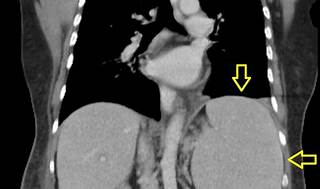

The patient's presentation is suggestive of splenic abscess, which is a rare but serious complication of splenomegaly. Splenic abscess is caused by bacterial or fungal infection of the spleen, usually from hematogenous spread or contiguous spread from adjacent organs. The most common symptoms are fever, chills, abdominal pain, and left shoulder pain (Kehr sign). The most significant laboratory finding is positive blood cultures, which indicate systemic infection and sepsis. Other laboratory findings may include leukocytosis, anemia, thrombocytopenia, elevated inflammatory markers, and abnormal liver function tests. However, these are nonspecific and may vary depending on the underlying cause of splenomegaly and the type of microorganism involved.